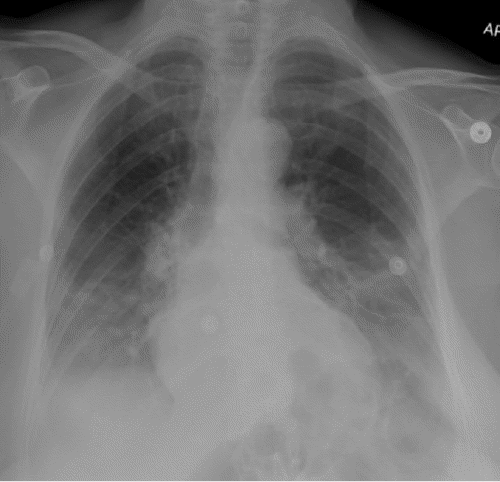

By hospital day 4, the patient was transferred to the floor. She had difficulty with the return of bowel function, but otherwise, she was doing well, working with physical therapy. On hospital day 8, she developed mild leukocytosis and tachycardia, prompting a chest X ray. This exam revealed a new, large diaphragmatic hernia, concerning for a traumatic hernia at the anterior diaphragm (Figure 1A). A review of a previous chest X ray confirmed that this was a new finding (Figure 1B). Aside from tachycardia, her vital signs were stable, and she was breathing comfortably on 2 L/min of oxygen. She denied new complaints at the time of the exam.

Figure 1. Diagnostic and Prior Chest X Rays. Published with Permission

A) Large hernia from left anterior diaphragm, concerning for traumatic hernia

B) Review of chest X ray from five days earlier demonstrated normal findings